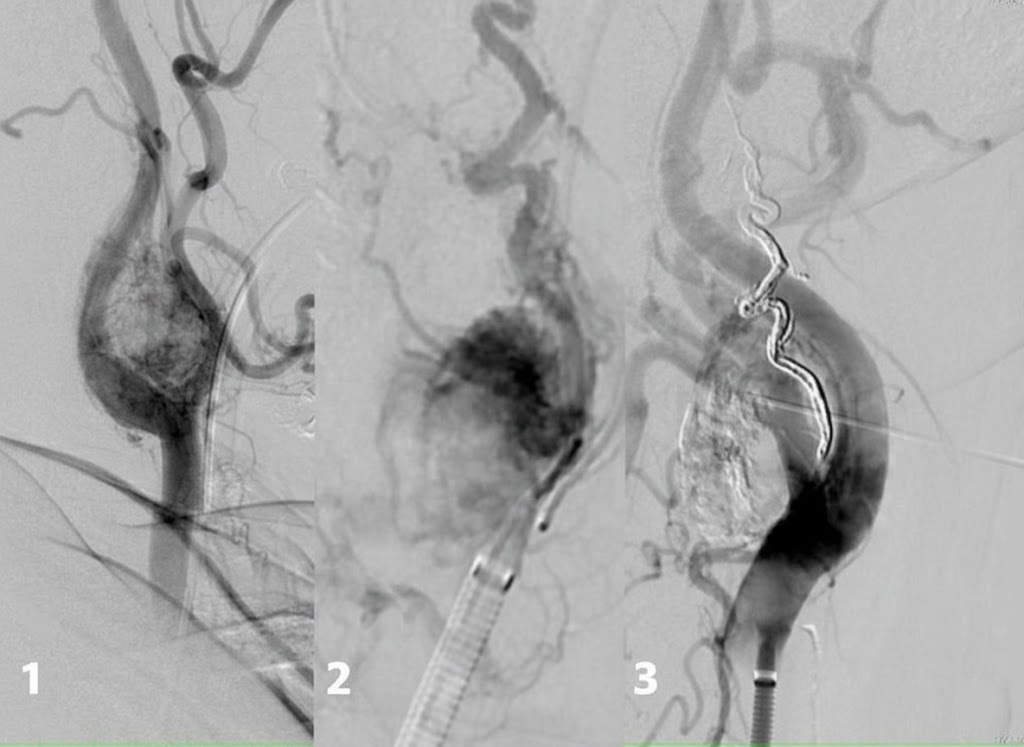

Ejemplo de arteriografía selectiva

🧯 Procedimiento de embolización: paso a paso

Punción femoral (generalmente)

Identificar pedículo nutricio

Blush tumoral, shunts

Micropartículas/coils

- 🔧 DSA con catéter selectivo en arteria nutricia principal.

- 🔧 Identificación de pedículos y shunts arteriovenosos.

- 🔧 Embolización con micropartículas, coils o líquidos embolizantes según objetivo.